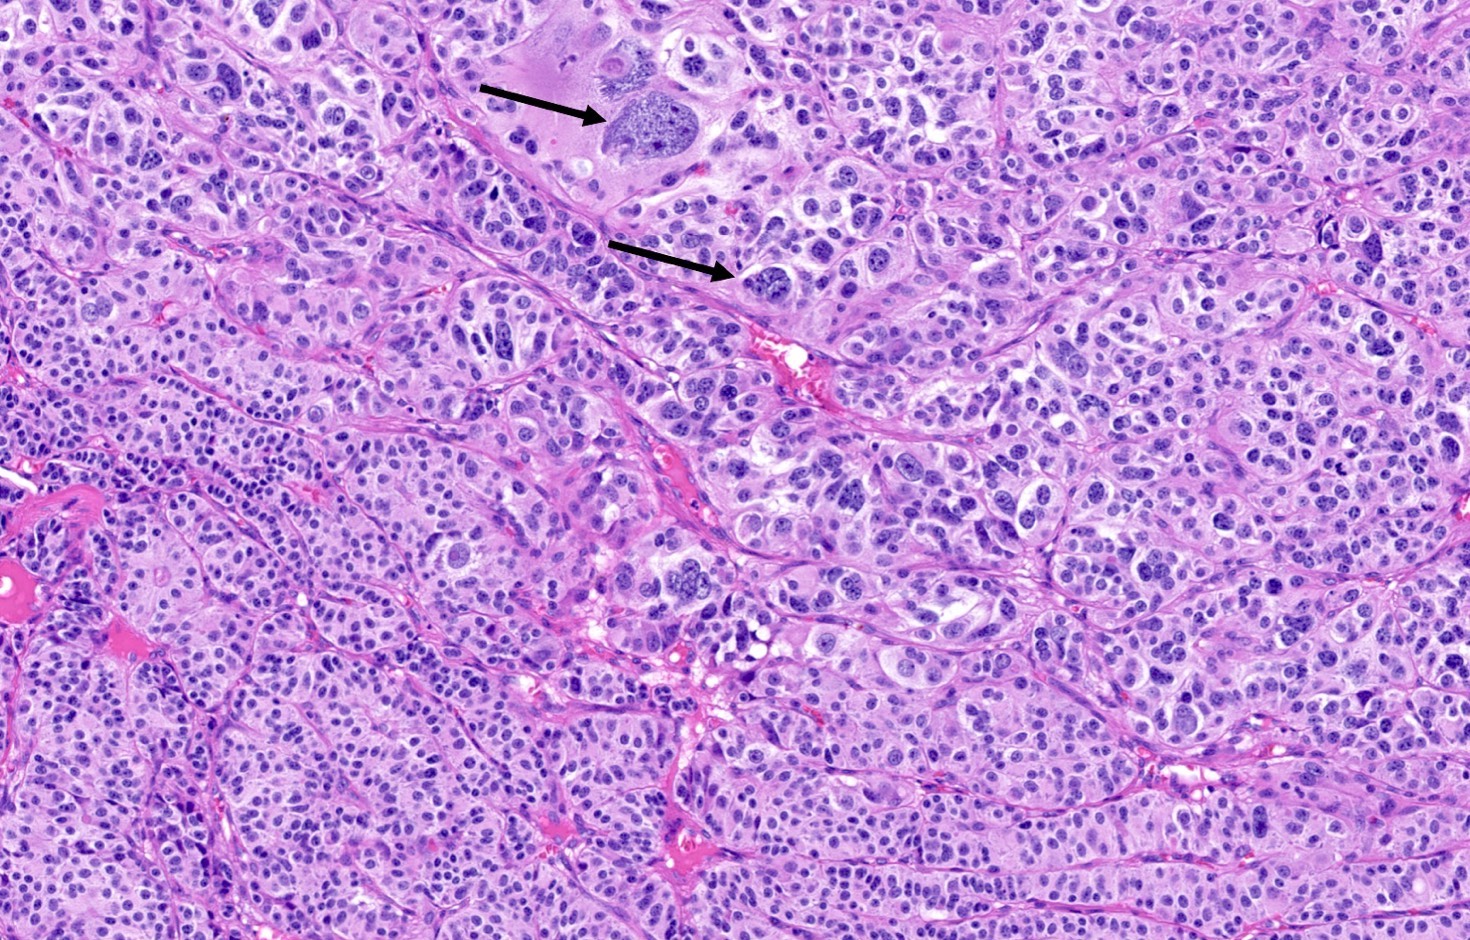

Microscopic (histologic) description

- Diagnostic criteria

- Neuroendocrine tumor with size ≥ 5 mm with < 2 mitoses/2 mm2 and absence of necrosis

- Neuroendocrine growth pattern (organoid, trabecular, rosette formation, nested) or pseudoglandular, follicular and papillary growth

- Tumor cells are uniform with a polygonal shape, round to oval nuclei with salt and pepper chromatin as well as inconspicuous nucleoli and moderate to abundant eosinophilic cytoplasm

- Spindle cells and clear cell features can be seen

- Stroma is fine and highly vascularized; hyalinization, cartilage or bone formation are possible

- Reference: Curr Oncol 2018;25:S86

Microscopic (histologic) images

Contributed by Philippe Joubert, M.D., Ph.D., Jijgee Munkhdelger, M.D., Ph.D. and Andrey Bychkov, M.D., Ph.D.

A 55 year old woman had a lower left lobectomy showing a well circumscribed flesh colored tumor. Histologic details are shown in the image above. Regarding this entity, which of the following statements is true?

A. CDX2 is usually negative in the lung and is useful to differentiate from a metastasis of an intestinal origin. The image shows a tumor with a trabecular pattern and pseudorosettes. The stroma is highly vascularized. Tumor cells are monotonous with scant to moderate eosinophilic cytoplasm. Nuclei are round to oval with salt and pepper chromatin and inconspicuous nucleoli. No mitoses are seen. These features are consistent with a typical carcinoid lung tumor.